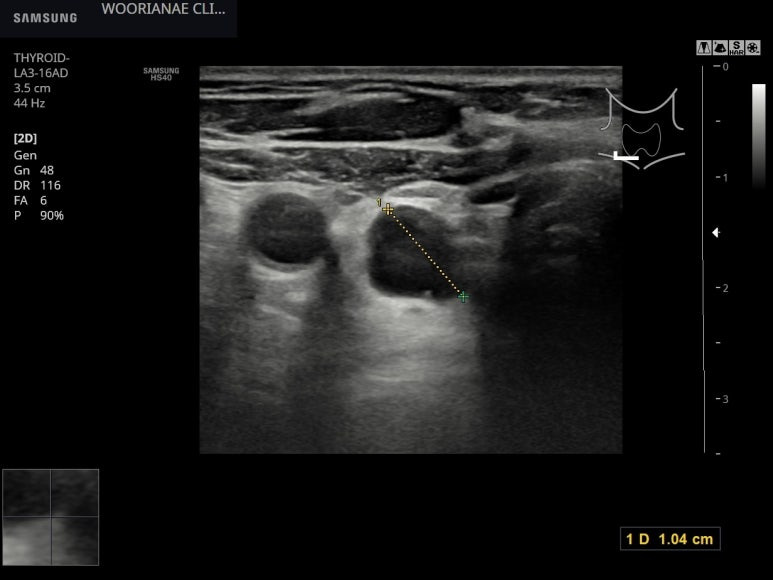

흡연하는 분으로 좌측 경동맥 아래쪽은 내막이 균일하게 두껍고...

상기 모습이 림프절에 가깝지 않으나 주변부 다른 림프절이 비대칭적으로 커져있나 찾아보는데 특별해 보이지 않으며.. 경동맥 아래 무명동맥까지 관찰